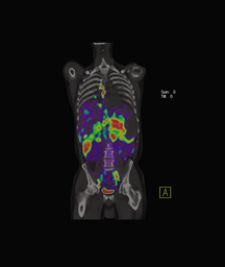

TOF helps to reduce imaging noise, which is associated with acquiring images of obese patients. “The idea of noise and the resultant lower quality images seen when imaging obese patients is not being discussed enough,” noted Dr. Osman. He finds this especially troubling given that a large number of patients being scanned today fall into a body mass index range of overweight to obese. His concern is strengthened by numerous studies released in the past several years discussing America’s obesity problem.

The quality of PET images for obese patients obtained on non-time of flight scanners, according to Dr. Osman, are suboptimal. “The two options typically used to make up for suboptimal images, specifically injecting more radioactive tracer into the patient and utilizing higher imaging timeframes, do not adequately compensate for the suboptimal image quality. The time-of-flight technology alleviates this suboptimal image,” said Dr. Osman. In his experience, TOF images exhibit a much higher quality on obese patients than those images acquired not using the technology, with injected tracer amounts and image acquisition parameters remaining the same during both image acquisitions.

Since the introduction of the Gemini, Suleman Surti, Ph.D., research assistant professor at the University of Pennsylvania, has led a study to evaluate its intrinsic TOF capability and its impact on the reconstructed images. Dr. Surti and his fellow researchers “performed experiments with this scanner using reproducible phantoms mimicking the presence of lesions in a patient.” The measurement capability of the new TOF scanner, when used to reconstruct an image, showed improved image quality and, in turn, allowed for more accurate detection of small lesions. The study concluded that “[t]his new time-of-flight scanner, used with LYSO detector crystals, will improve the diagnostic accuracy of images, potentially leading to improved sensitivity and specificity in cancer lesion detection tasks in heavy patients.” However, Dr. Surti also mentioned, “Our data indicates that more robust measures are needed to fully quantify the gains in imaging quality and to better define the relationship of image quality to patient size and timing resolution.”